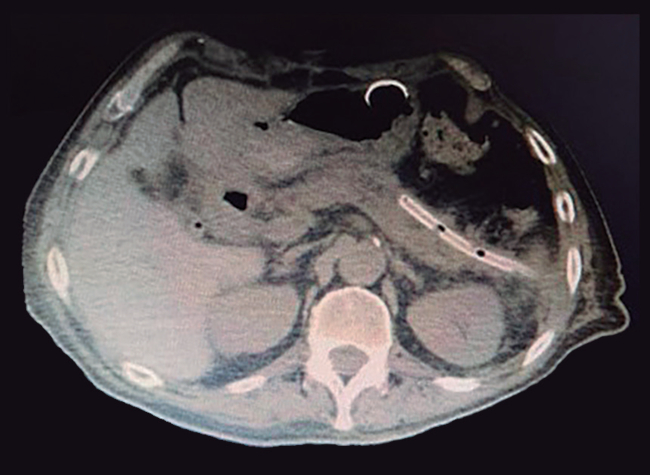

El paciente evoluciona favorablemente con mejoría clínica y tomográfica. Se retira el stent luego de la última sesión y se coloca un drenaje, permaneciendo un escaso débito por diez días, con niveles de amilasa normal, dejándose curar el tracto fistuloso por intención secundaria (Figura 5). El paciente continuó dos semanas internado para control evolutivo, con posterior alta hospitalaria.